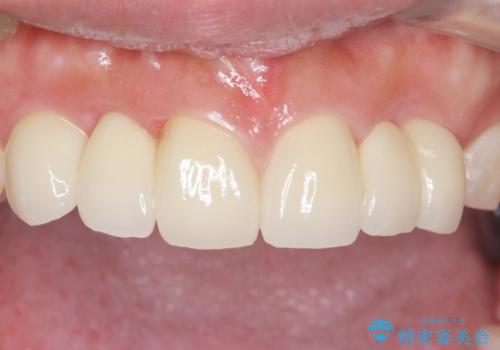

自然な仕上がりにご満足頂けました。

治療終了後、奥歯に残っていた矯正の接着剤を除去し、ホワイトニングも行いました。

クラウンの種類:オールセラミッククラウン スタンダード